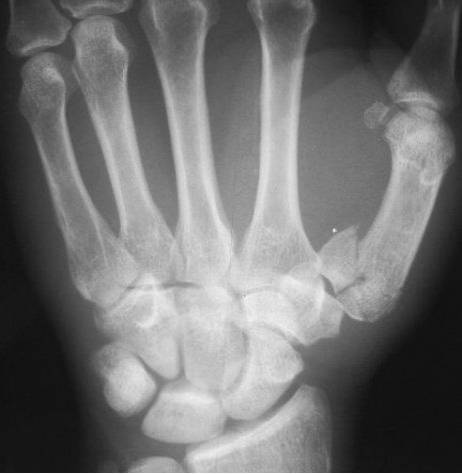

Boxer骨折

拳击骨折:指第5掌骨颈骨折,伴有掌骨头向掌侧移位,骨折端背侧成角,多发生于握拳击打损伤所致,同样的损伤机制,第4掌骨颈部骨折,也称Boxer骨折。